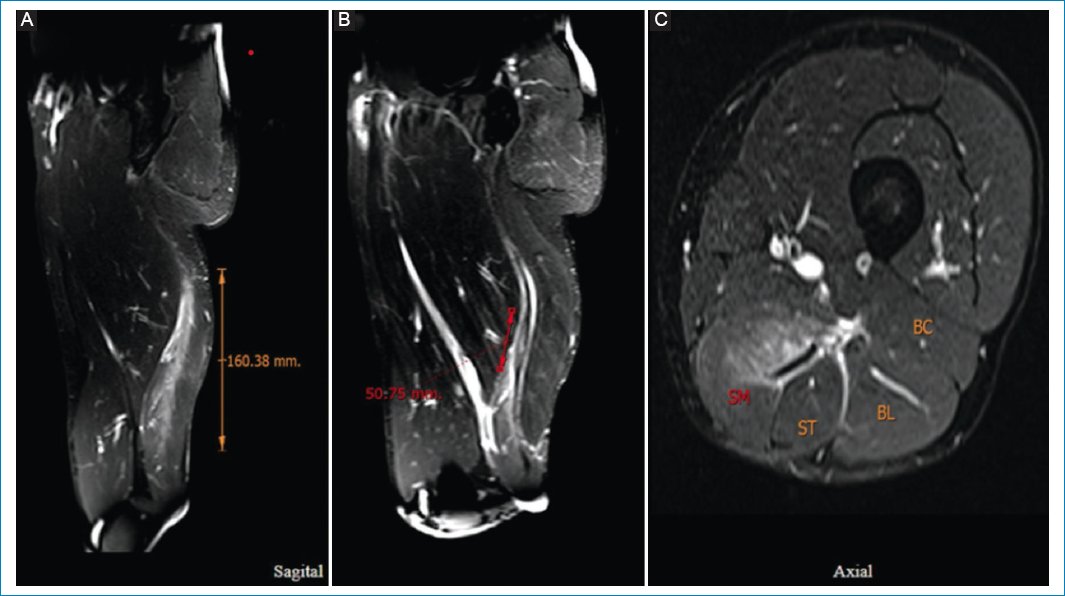

El sistema de clasificación utiliza como método la RM para confirmar el diagnóstico clínico de disrupción, proporcionando información sobre la ubicación, el área de la sección transversal (AST) y la extensión del desgarro2 (Fig. 1). Describe una combinación de extensión de la lesión (grados 0 a 4) y sitio anatómico (a, b y c).

Figura 1. (A) Imagen de RM con supresión grasa de muslo izquierdo. (B) Muestra una lesión del semimembranoso, en la unión miotendinosa, con edema muscular > 15 cm. (C) distorsión del tendón > 5 cm, el área de la sección transversal involucra el 50% del vientre muscular. British Athletics Muscle Injury Classification (BAMIC) 3b/c.